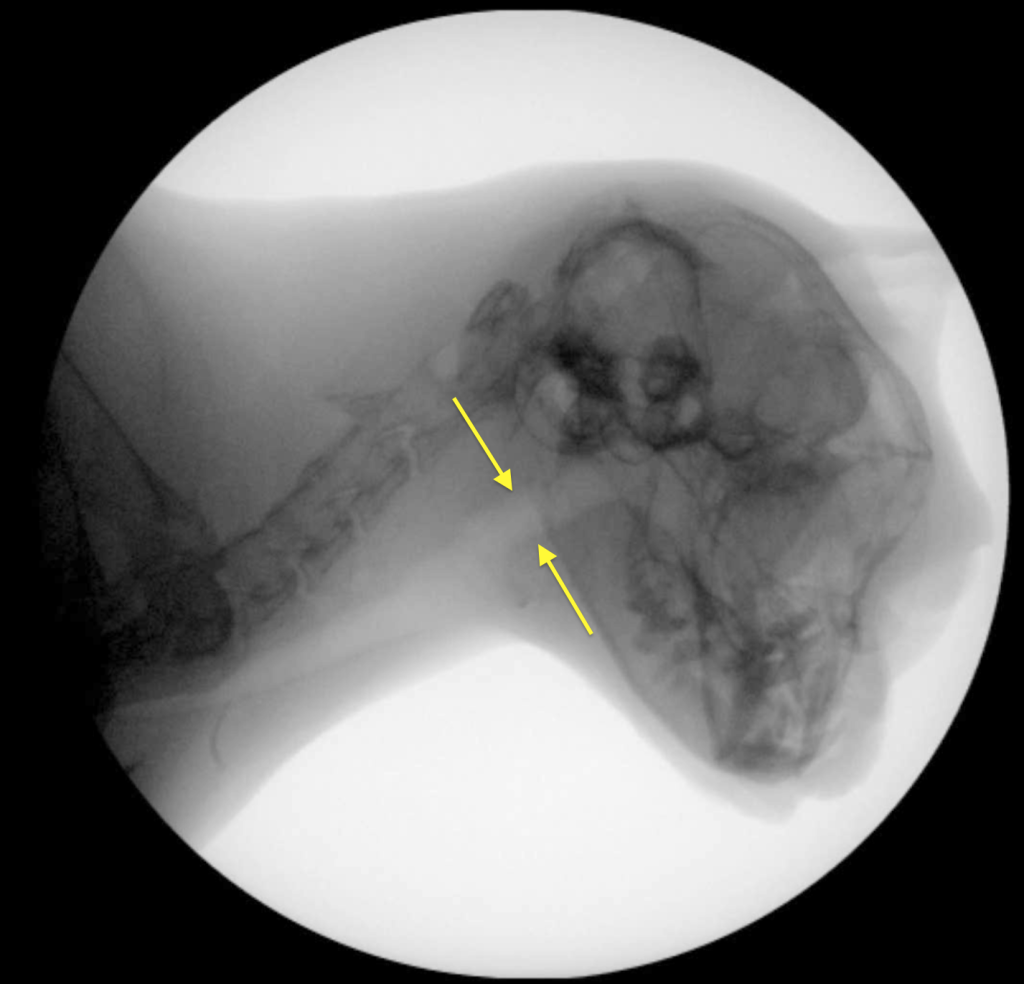

Коллапс обычно происходит во время вдоха, следовательно, это не длительное, а динамическое отклонение. Динамический назофарингеальный коллапс может быть как первичной, так и вторичной патологией5. У людей ДНФК был признан основной причиной синдрома обструктивного апноэ во сне (англ. obstructive sleep apnea syndrome; OSAS), однако в ветеринарии мелких домашних животных это состояние описывается редко, особенно у кошек5. Несмотря на сходные механизмы обструкции носоглотки у людей, собак и кошек, динамический коллапс у людей преимущественно проявляется во время сна7,8 в отличие от кошек и собак, у которых наиболее выраженные приступы одышки наблюдаются во время физической нагрузки или стресса1,2,3,5. Возможно, попытки экстраполировать методы лечения данной патологии из медицины человека являются ошибочными8.Золотым стандартом для подтверждения диагноза «динамический назофарингеальный коллапс у кошек» является рентгеноскопия акта дыхания1,2,5.

Рентгеноскопия акта дыхания проводится без седации, в естественном сидячем или стоячем положении животного.

У одного пациента коллапс проявлялся только на глубоком вдохе, у остальных трех кошек – на каждом вдохе (возможно, само исследование было стрессом для животных, что провоцировало их делать глубокие вдохи).